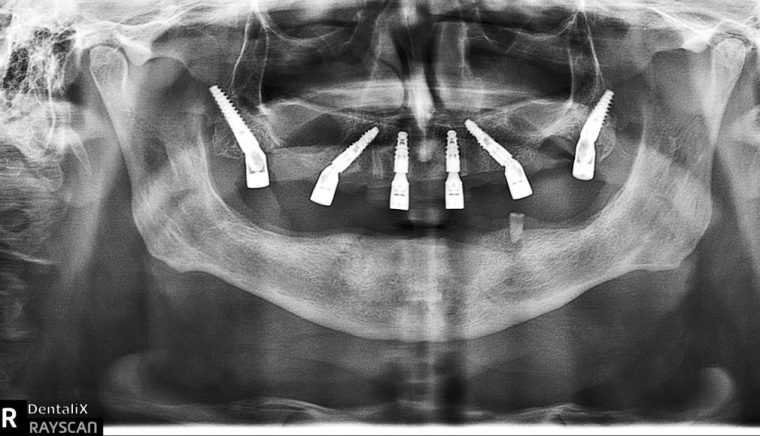

Într-un domeniu în care reabilitările totale ale danturii – precum procedurile All-on-4 sau All-on-6 – pot dura zile sau chiar săptămâni, Dentalix a spart tiparele: cu ajutorul tehnologiei de ultimă generație și al unei echipe extrem de bine coordonate, dr. Negru și colegii săi au reușit să finalizeze astfel de intervenții complexe în doar o oră! Aceasta înseamnă că pacienții pot intra în clinică fără dinți funcționali și pot ieși după 60 de minute cu arcada complet restaurată și funcțională – un veritabil „zâmbet nou pe repede înainte”!